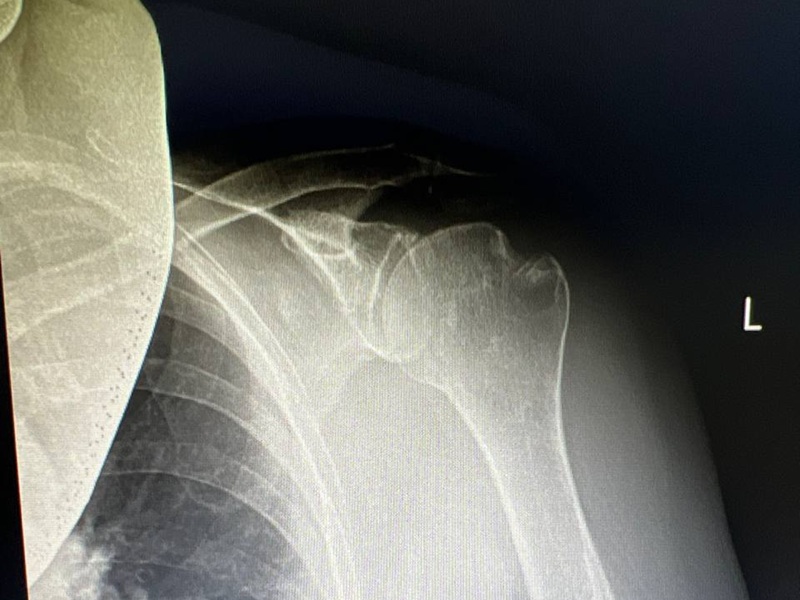

Остеосинтез плеча вивих ДО-ПІСЛЯ: